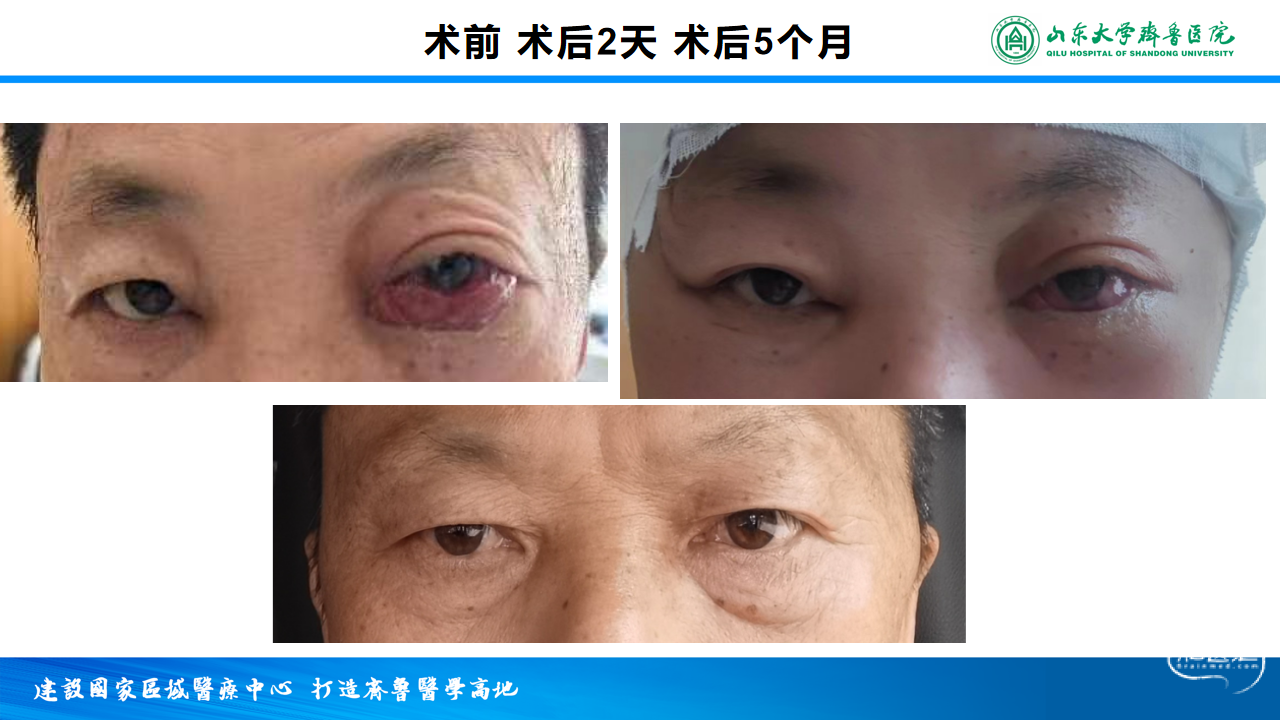

左眼红肿8月,左眼球突出半月

患者8月前出现左眼红肿,多泪,于当地医院就诊,行颅脑CT及脑血管造影检查结果示颈内动脉动静脉瘘,未做特殊处理,半月前出现左眼球突出,为求进一步治疗,特来院就诊

双侧ICA造影见DAVF消失